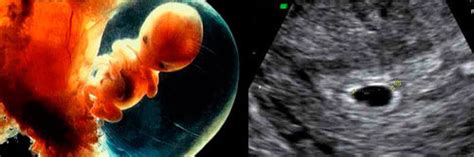

Dublu test, cunoscut și sub denumirea de bitest sau test combinat, este o investigație de screening prenatal efectuată în primul trimestru de sarcină. Acesta măsoară doi markeri biochimici din sângele femeii însărcinate pentru a estima riscul de anomalii cromozomiale la făt, cum ar fi Sindromul Down (trisomia 21), Sindromul Edwards (trisomia 18) și Sindromul Patau (trisomia 13).

Testul combină analiza a doi hormoni placentari circulanți în sângele matern: proteina A plasmatică asociată sarcinii (PAPP-A) și gonadotropina corionică umană liberă (free beta-hCG). De asemenea, rezultatele dublului test sunt corelate cu datele obținute în urma unei ecografii de translucență nucală (mărimea spațiului cu lichid din zona cefei fătului) și cu factori materni.

- Măsurarea translucenței nucale (NT): Grosimea spațiului cu lichid creat în mod normal în zona cefei fătului. O translucență nucală crescută poate fi un indicator al unui risc mai mare de anomalii cromozomiale.